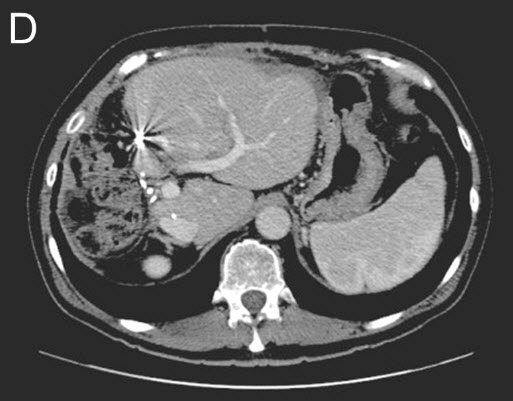

| (D) Stage II - Second Surgery: The right liver and tumors are removed. CT-Scan shows additional growth (hypertrophy) of the remaining liver remnant. |